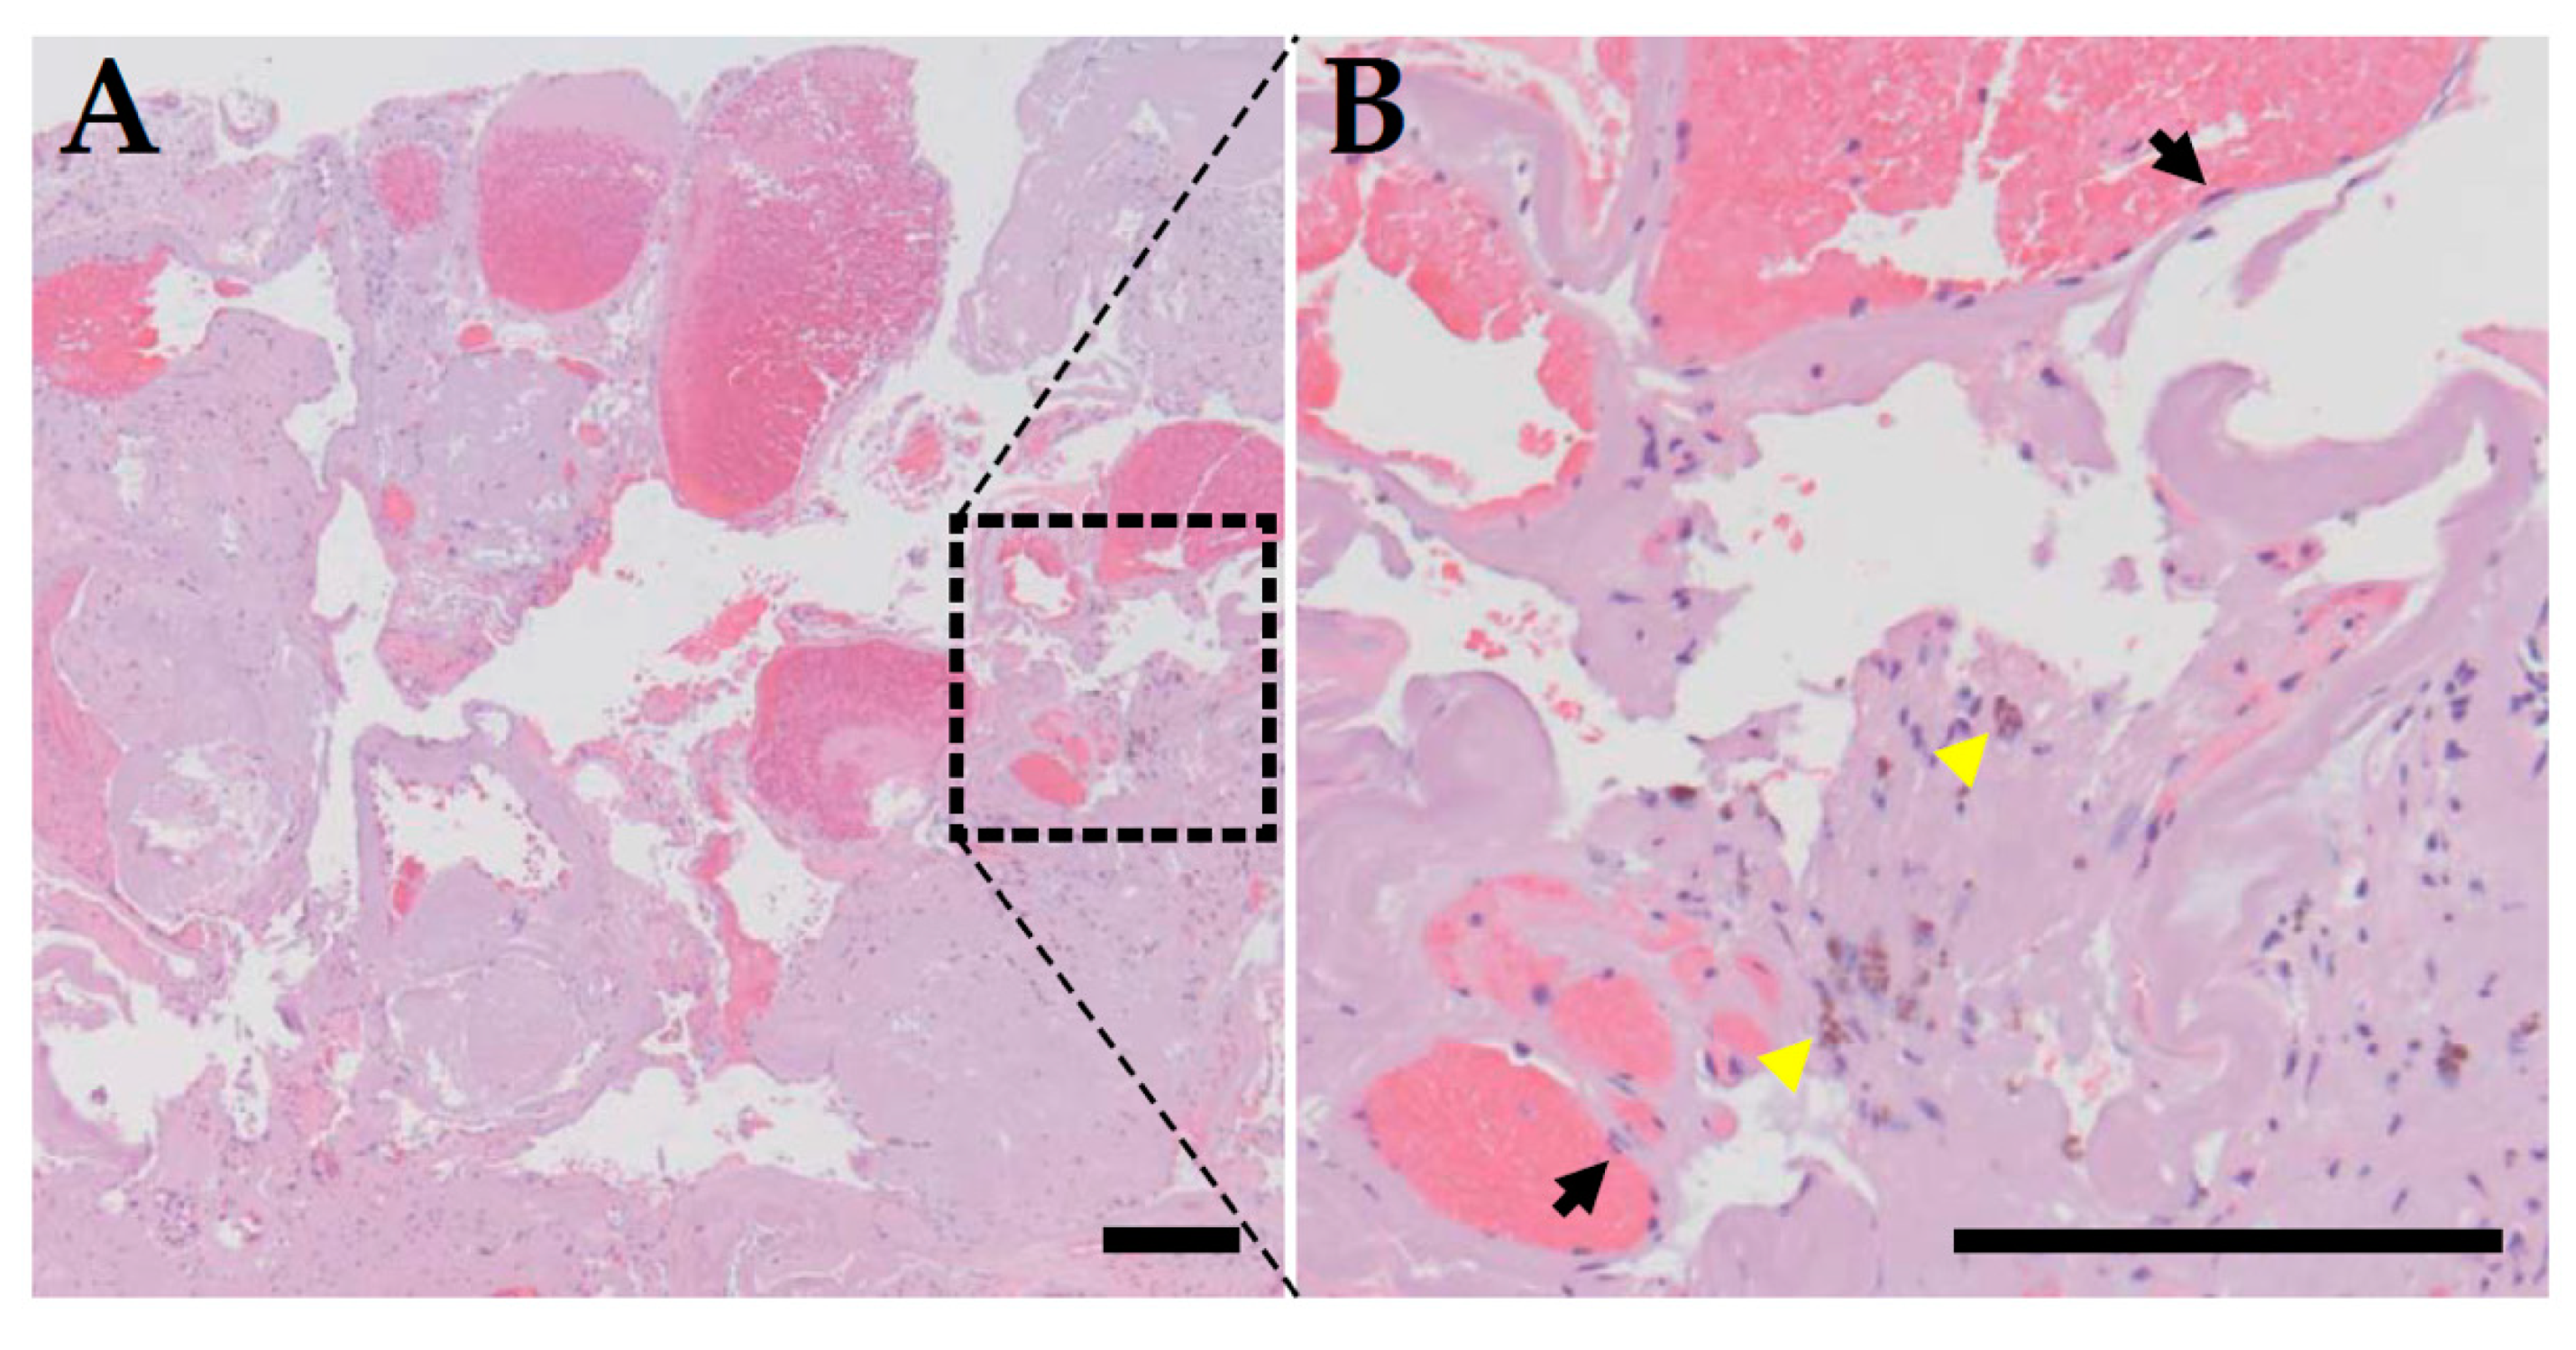

- Wong, J.H.; Awad, I.A.; Kim, J.H. Ultrastructural pathological features of cerebrovascular malformations: A preliminary report. Neurosurgery 2000, 46, 1454–1459. [Google Scholar] [CrossRef] [PubMed]

- Tu, J.; Stoodley, M.A.; Morgan, M.K.; Storer, K.P. Ultrastructural characteristics of hemorrhagic, nonhemorrhagic, and recurrent cavernous malformations. J. Neurosurg. 2005, 103, 903–909. [Google Scholar] [CrossRef]

- Girard, R.; Fam, M.D.; Zeineddine, H.A.; Tan, H.; Mikati, A.G.; Shi, C.; Jesselson, M.; Shenkar, R.; Wu, M.; Cao, Y.; et al. Vascular permeability and iron deposition biomarkers in longitudinal follow-up of cerebral cavernous malformations. J. Neurosurg. 2017, 127, 102–110. [Google Scholar] [CrossRef]

- Mikati, A.G.; Khanna, O.; Zhang, L.; Girard, R.; Shenkar, R.; Guo, X.; Shah, A.; Larsson, H.B.; Tan, H.; Li, L.; et al. Vascular permeability in cerebral cavernous malformations. J. Cereb. Blood Flow Metab. 2015, 35, 1632–1639. [Google Scholar] [CrossRef]